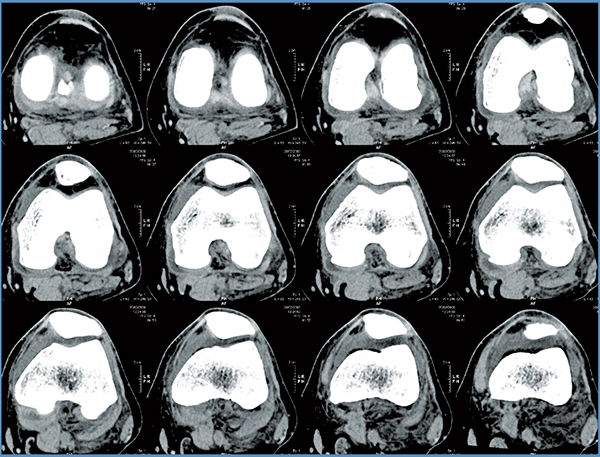

Mako Robotic-Arm Assisted Technology provides you with a personalized surgical plan based on your unique anatomy. First, a CT scan of the diseased knee joint is taken. This CT scan is uploaded into the Mako System software, where a 3D model of your knee is created. This 3D model is used to pre-plan and assist your surgeon in performing your partial knee replacement.

Step 1. Knee CT Scan

Step 2. Knee Personalized Planning